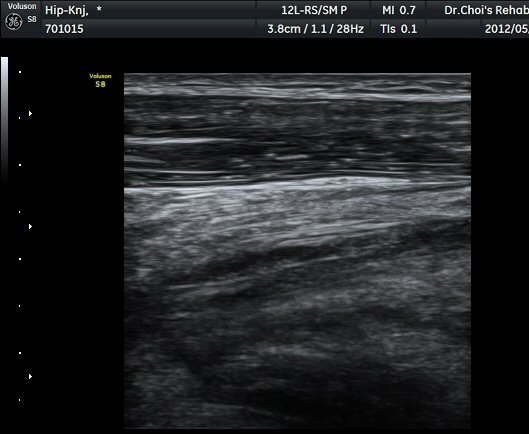

´ëÅðÁ÷±Ù Á¾´Ü¸é°Ë»ç¿¡¼­ ±ÙÀ°³»¿¡ ¼±»óÀÇ Àú¿¡ÄÚ °¢±ØÀÌ °üÂûµÈ´Ù(±×¸² 4, 5).